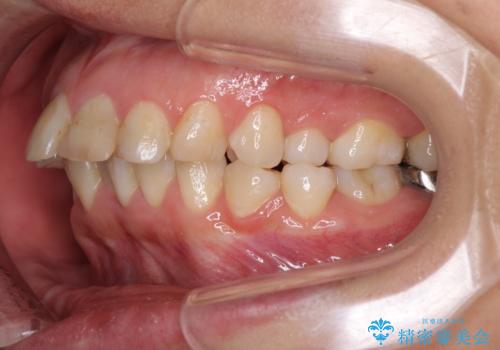

矯正治療後は、気になっていた銀歯を全てセラミックとし、きれいな口元に仕上げることができました。